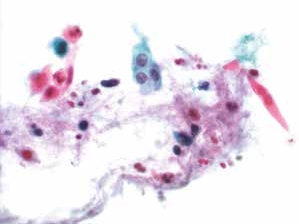

癌细胞成团排列,细胞核异型性明显,染色质粗颗粒状,胞质蓝染,高核质比,肿瘤素质可见。

图4-69 非角化型鳞癌(高倍、液基、巴氏染色)

癌细胞成团排列,圆形、梭形,胞核深染,染色质粗颗粒状,核质比高,肿瘤素质可见。

图4-70 非角化型鳞癌(高倍、液基、巴氏染色)